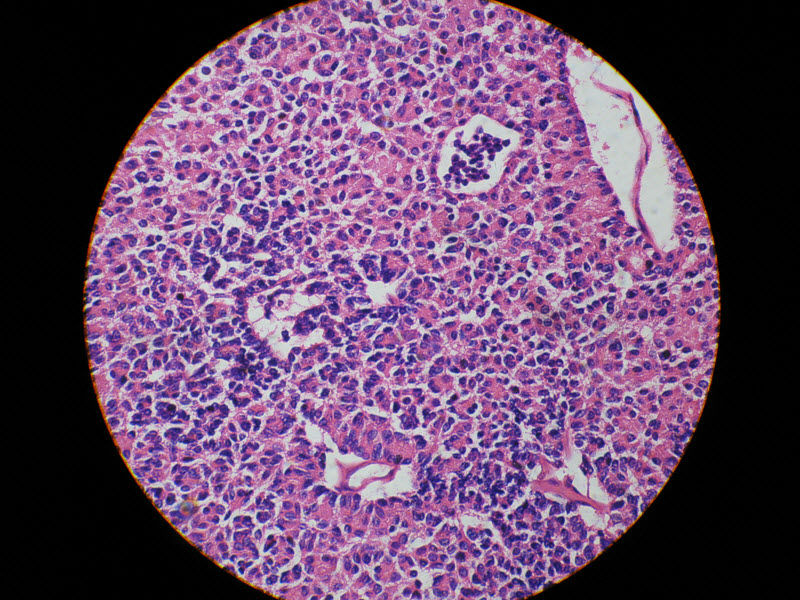

肾脏肿瘤,请教诊断!图3

名称:图3

描述:20倍

肾脏肿瘤,请教诊断!图4

名称:图4